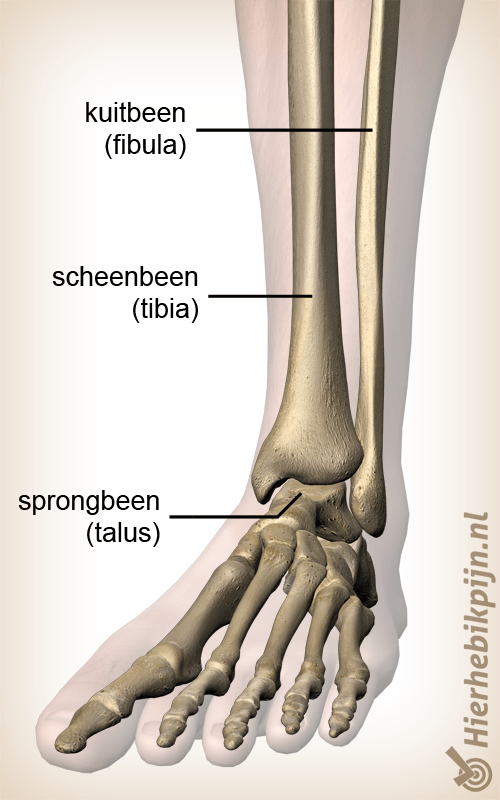

Enkel